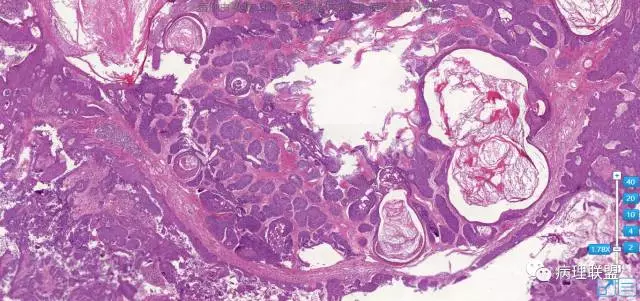

病例2

女。59,眼睑肿物

图片信息

@左淑英 1毛囊瘤,2毛发上皮瘤。3是钙化上皮瘤。4是外毛根鞘瘤

四个病例,有点混乱了。3钙化上皮瘤。4增生性外毛根鞘瘤,2毛母细胞瘤,1分不清了毛囊分化,请左老师有时间讲解一下